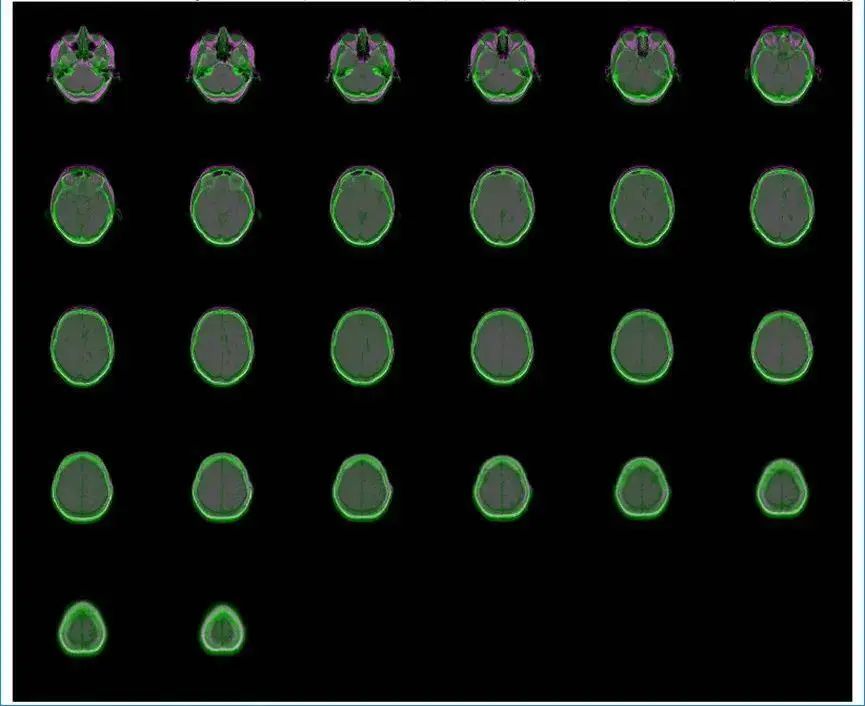

4.醫(yī)學圖像工具箱

醫(yī)學圖像分析對于現(xiàn)代醫(yī)療診斷極為重要。北太天元的醫(yī)學圖像工具箱提供了一系列實用函數(shù),可聯(lián)合圖像處理工具箱、計算機視覺工具箱,用于醫(yī)學圖像的預處理,去除圖像噪聲,增強圖像質(zhì)量;進行圖像配準,使不同模態(tài)的醫(yī)學圖像能夠準確對齊;實現(xiàn)圖像標注和分割,精確勾勒出病變區(qū)域等。在醫(yī)學建模競賽中,可利用此工具箱對CT、MRI等醫(yī)學圖像進行分析,為疾病診斷模型提供有力支持。